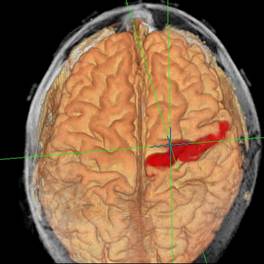

Schließlich gelingt mit Hilfe der Kernspintomografie heute auch die Abgrenzung funktioneller Gehirnareale (fMRT) Motorkortex-Darstellung im fMRT bzw. die Darstellung von Bahnsystemen im Gehirn (Diffusion Tensor Imaging = DTI). Pyramidenbahn in DTI-Darstellung.

Eine Untersuchung mittels Kernspintomographie während der Operation trägt so unter Umständen dazu bei, dass der Tumor radikal, aber gleichzeitig schonend entfernt werden kann. Außerdem können Grenzen von Bahnsystemen und funktionelle Regionen im Gehirn dargestellt werden, die mit bloßem Auge unter dem Mikroskop nicht sichtbar sind.

Die Kernspintomografie bietet auch eine gute Möglichkeit, anhand der gewonnenen Informationen über Lokalisation und Ausdehnung des Tumors weitere Schritte in der Behandlung zu planen - zum Beispiel die Erstellung eines Bestrahlungsplans.

Spezielle MRT-Verfahren wurden außerdem entwickelt, um zusätzlich zu Lage und Form der Organe auch Informationen über ihre Mikrostruktur und Funktion (besonders ihre Durchblutung) darzustellen.